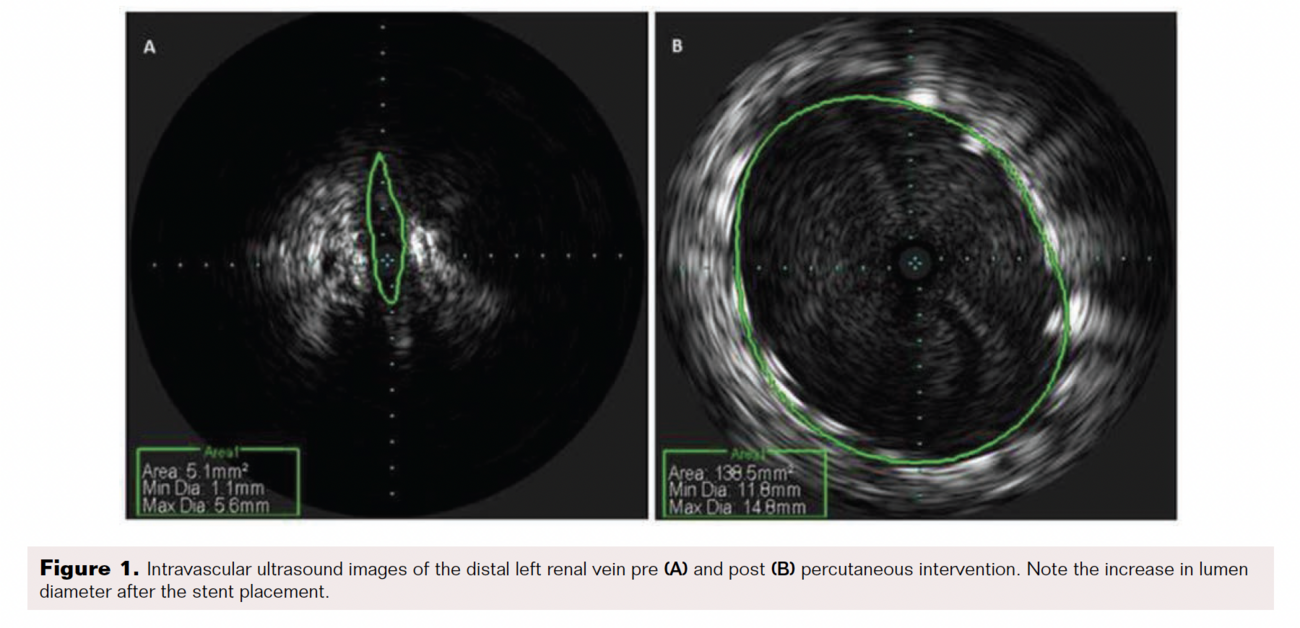

A 34-year-old woman with a history of hypotension, anemia, and asthma was referred to the cardiology clinic for evaluation of pelvic congestion syndrome (PCS). She reported longstanding constant, diffuse, progressively worsening, dull, aching pelvic and lower abdominal pain, exacerbated by exertion and sexual intercourse, for almost 2 years. She was amenorrheic and taking depot medroxyprogesterone for the past 2 years. Physical exam was significant for normal vital signs and tenderness over the lower abdominal quadrants, bilateral levator, and lumbar spine. Labs were significant for hemoglobin (10.7 mg/dL), hematocrit (33.4%), and microscopic hematuria. Computed tomography (CT) scan of the abdomen and pelvis with contrast was significant for mild right-sided hydronephrosis and a 3 mm right distal ureteral calculus. Transabdominal and transvaginal pelvic ultrasound showed prominent pelvic vasculature with a small amount of free pelvic fluid, suggestive of PCS. Inferior vena cava (IVC) venography and renal vein angiography with intravascular ultrasound (IVUS) was performed with a high suspicion for nutcracker syndrome (Figure 1). It revealed a normal IVC, a dilated proximal left renal vein (LRV) and gonadal vein with varicose veins, and a complete obliteration of the lumen from the mid to distal LRV adjacent to the superior mesenteric artery (SMA). Balloon angioplasty with an 8.0 balloon and self-expanding 14 x 4 cm stent was placed in the LRV, overlapping with another 6 x 4 cm stent. IVUS after stent placement revealed the dimension of the LRV to be 40 mm, with no compression at the end of the procedure. The patient was started on aspirin and clopidogrel and was followed up in clinic.